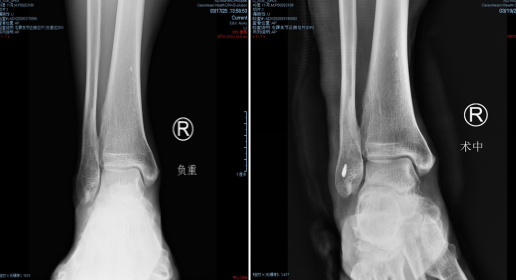

手术入路——两个0.5厘米小孔

石院长给他做了仔细检查,结合片子,确诊为“右踝外侧韧带损伤”。两天后,石院长李亮医生给患者进行了踝关节镜下右踝探查清理+距腓前韧带修复手术。

术中,探查见关节腔大量增生病变滑膜组织,距骨软骨面多处软骨剥脱变性,明显的外侧副韧带损伤后继发关节炎表现。手术医生在踝关节镜下刨削刺激病变的距骨软骨,打入锚钉固定距腓前韧带,圆满完成手术。